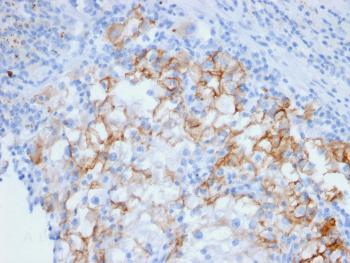

Fig.1: Formalin-fixed, paraffin-embedded human Renal Cell Carcinoma stained with Cadherin 16 Mouse Monoclonal Antibody (CDH16/2448).

ELISA (For coating, order Ab without BSA);Immunohistochemistry (Formalin-fixed) (1-2ug/ml for 30 minutes at RT)(Staining of formalin-fixed tissues requires heating tissue sections in 10mM Tris with 1mM EDTA, pH 9.0, for 45 min at 95°C followed by cooling at RT for 20 minutes);